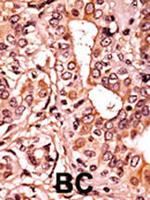

CDK7 Polyclonal Antibody

高级验证

6

种属

Human Mouse

类型

Rabbit Polyclonal

应用

WB IHC (P) IP

货号 PA5-34791

100 µL